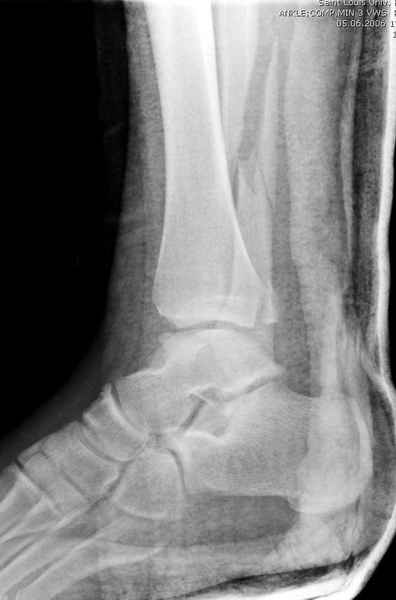

Конечно, компьютерный томограф более информативный метод, но с помощью недорогого обычного стандартного в нейтральном положении стопы: прямого, бокового и косой (ankle mortise) ренгенологического метода можно получить полную информацию о повреждении голеностопного сустава, а сравнительный снимок с другой стороны подтвердить наличие повреждения.

При реконструкции голеностопа, о важности восстановления длины малоберцовой для профилактики пост травматического артроза разбирали в предыдущих дискуссиях. Нарушенную биомеханику голеностопа без восстановления длины малоберцовой, не восстановить только швом медиальной связки.

Расширенная медиальная щель более чем на 4 мм и укорочение малоберцовой более чем 2 мм, а перелом заднего края большеберцовой смещения более 2мм с вовлечением 30% поверхности сустава, считается отходом от нормы голеностопного сустава, и подлежит к оперативному вмещательству.

Здесь похожий случай трехнедельной давности, перелом почти сросся и была укорочена малоберцовая, на операции длину малоберцовой смогли восстановить только после того, когда проксимальнее пластины ввели шуруп и использовали его как толкатель, с помощбю дистракционого инструмента (lamina spreader).

Меньше всего волнует положение медиальной лодыжки - в любое время можно провести остео или реостеосинтез, при несращении можно просто резецировать без ущерба для движений в голеностопе. Здесь обошлись фиксацией одним 4 мм канюлированным шурупом.